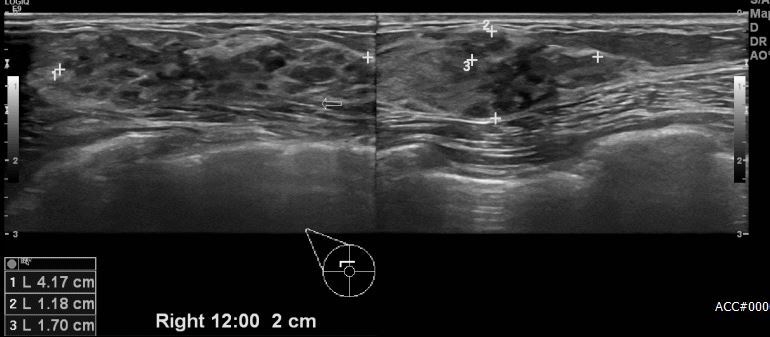

상기환자 유방의 멍울로 결과 관찰하시는 40대 여성분으로 우측 12시 방향에서 2cm 떨어진 거리의 혹 조직검사 시행하여 비정형 유두종양 진단 되어 맘모톰 시행하여 우측 유관암

진단되었습니다.